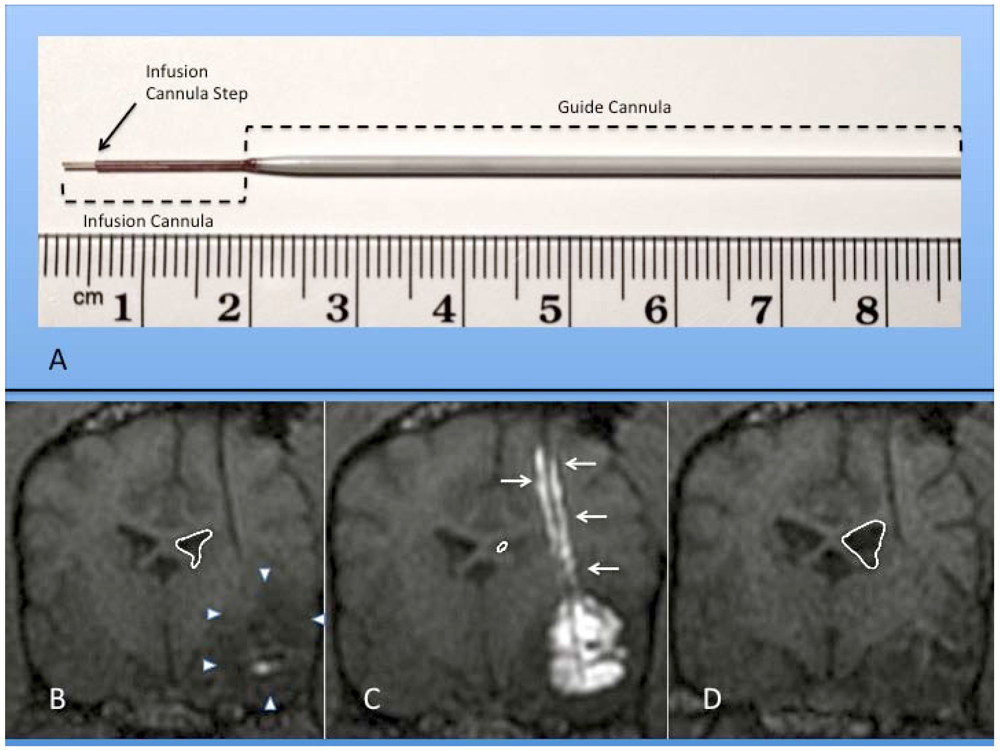

- Krauze, M.T.; Saito, R.; Noble, C.; Tamas, M.; Bringas, J.; Park, J.W.; Berger, M.S.; Bankiewicz, K.S. Reflux-free cannula for convection-enhanced high-speed delivery of therapeutic agents. J. Neurosurg. 2005, 103, 923–929. [Google Scholar] [CrossRef] [PubMed]

- Fiandaca, M.S.; Varenika, V.; Eberling, J.; McKnight, T.R.; Bringas, J.; Pivirotto, P.; Beyer, J.; Hadaczek, P.; Forsayeth, J.; Bowers, W.J.; et al. Real-time MR imaging of adeno-associated viral vector delivery to the primate brain. Neuroimage 2009, 47, 27–35. [Google Scholar]

- Saito, R.; Krauze, M.T.; Bringas, J.R.; Noble, C.; McKnight, T.R.; Jackson, P.; Wendland, M.F.; Mamot, C.; Drummond, D.C.; Kirpotin, D.B.; et al. Gadolinium-loaded liposomes allow for real-time magnetic resonance imaging of convection-enhanced delivery in the primate brain. Exp. Neurol. 2005, 196, 381–389. [Google Scholar] [CrossRef] [PubMed]

- Krauze, M.T.; McKnight, T.R.; Yamashita, Y.; Bringas, J.; Noble, C.O.; Saito, R.; Geletneky, K.; Forsayeth, J.; Berger, M.S.; Jackson, P.; et al. Real-time visualization and characterization of liposomal delivery into the monkey brain by magnetic resonance imaging. Brain Res. Protoc. 2005, 16, 20–26. [Google Scholar] [CrossRef]

- Varenika, V.; Dickenson, P.; Bringas, J.; LeCouteur, R.; Higgins, R.; Park, J.; Fiandaca, M.; Berger, M.; Sampson, J.; Bankiewicz, K.S. Detection of infusate leakage in the brain using real-time imaging of convection-enhanced delivery. J. Neurosurg. 2008, 109, 874–880. [Google Scholar] [CrossRef] [PubMed]